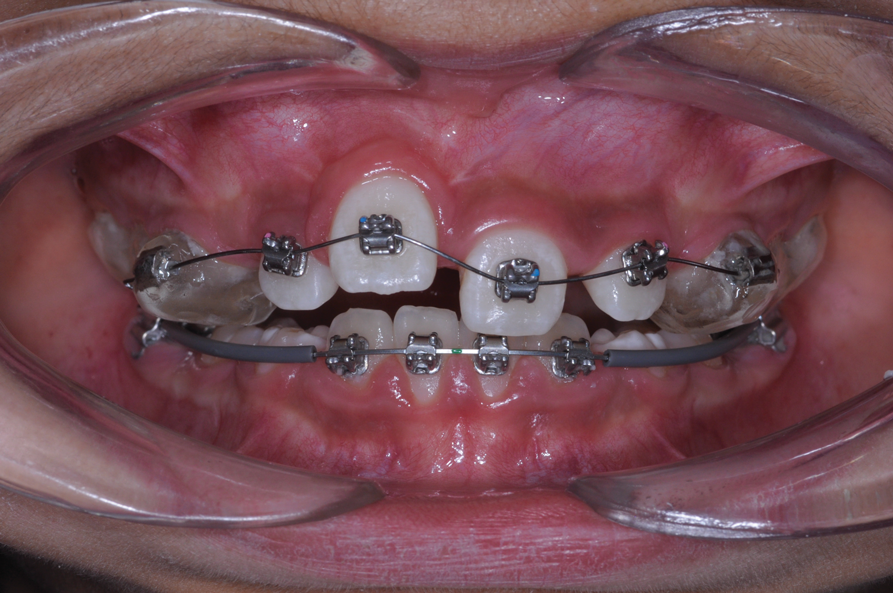

The maxillary right permanent centralincisor had a delayed eruption of 1½ years compared to its homologous incisor, and it was anteriorly displaced due to insufficient space in the premaxilla. Removal of the maxillary deciduous canines was indicated to unravel the crowding. An apically positioned flap of the impacted right central incisor was made to facilitate its eruption (Figure 5 and Figure 6). The case was worked up to plan an active phase l treatment, consisting of palatal expansion and the use of sectional fixed appliances in the upper arch. A transverse deficiency without posterior crossbite was identified, and therefore palatal expansion with a bonded expander was planned to widen the premaxilla (Figure 7 and Figure 8). A two-by-four fixed appliance system (brackets in the four maxillary anterior teeth and bands on the maxillary first molars) was used to align the maxillary teeth. The gingival margin of the retained maxillary right central incisor was slightly more apical than the left one, which erupted as expected (Figure 9 and Figure 10). Figure 11 shows a panoramic radiograph taken after completion of phase 1 treatment.

Fig 7. Clinical situation after rapid palatal expansion and orthodontic traction, frontal view (Fig 7) and occlusal view (Fig 8).

Figure 7

Fig 8. Clinical situation after rapid palatal expansion and orthodontic traction, frontal view (Fig 7) and occlusal view (Fig 8).

Figure 8